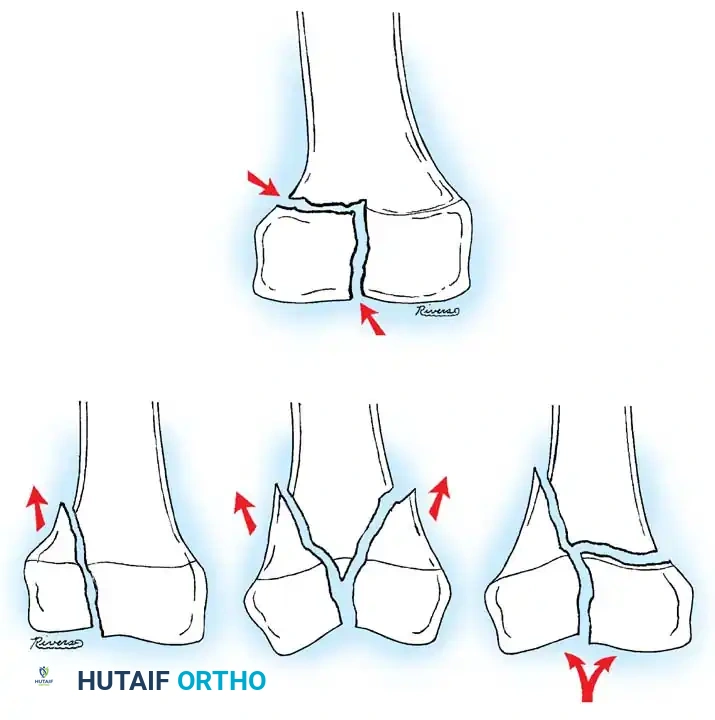

- Proximal Shaft and Subtrochanteric Fractures: The proximal fragment is typically driven into flexion, abduction, and external rotation. This is due to the unopposed pull of the iliopsoas (flexion), the gluteus medius and minimus (abduction), and the short external rotators.

- Midshaft Fractures: The adductors and extensors remain intact. The distal fragment is usually in satisfactory alignment, albeit with a tendency toward external rotation and proximal migration (shortening) due to the adductor magnus and quadriceps.

- Supracondylar Fractures: The distal fragment is pulled into hyperextension due to the strong origin of the gastrocnemius muscle on the posterior femoral condyles.

DISTAL FEMORAL PHYSEAL AND SUPRACONDYLAR FRACTURES

Fractures involving the distal femoral physis (Salter-Harris types) or the supracondylar region require distinct management. The distal femoral physis contributes 70% of the growth of the femur and 40% of the overall growth of the lower extremity. Consequently, anatomic reduction is paramount to minimize the risk of premature physeal closure and subsequent limb-length discrepancy or angular deformity.